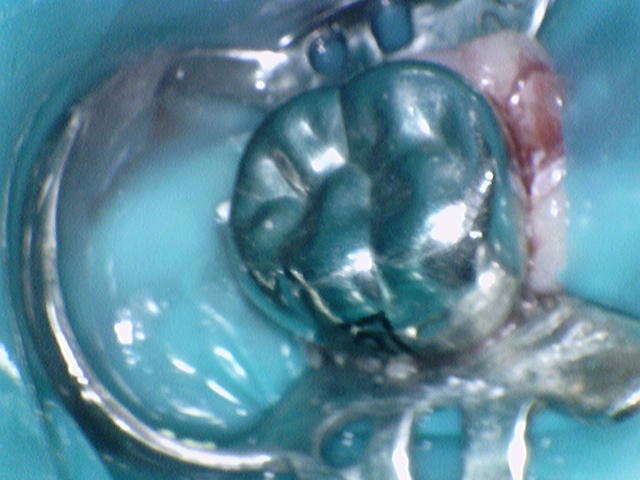

타 소아치과에서 치료하지 못한다고 했던 이는 어떻게 치료했을까요?

치료 전. 치아의 반 넘게 충치로 깨져있습니다.

치료 후. 깨끗하게 신경치료 후 잘 기능할 수 있도록 영구치 SS 크라운을 씌워줬습니다. 아이가 다 성장하고 교합이 완성되면 성인 보철이 한번 필요합니다.